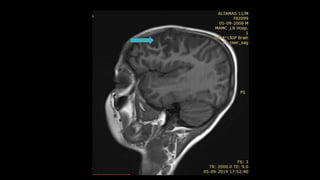

• #21 Here is an example. T2 axial and T1 Saggital image show focal altered signal intensity area on the left side of the medulla appearing hyperintense on T2 and hypointense on T1

• #38 Here is the T1 SAGITTAL image of a patient showing hypointensity in right FRONTOPARIETAL REGION

• #82 THIS IS THE SAGGITAL T1 W MRI BRAIN IMAGE SHOWING area of T1 HYPOINTENSITY IN CORONA RADIATA REGION